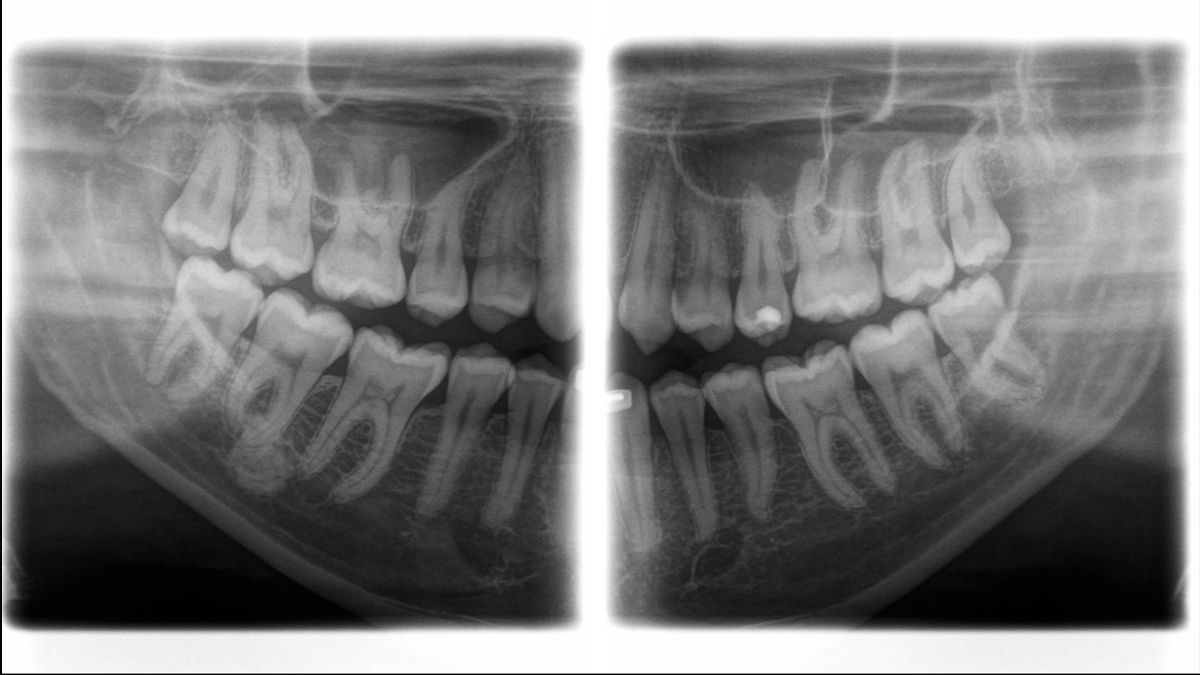

Orthophos SL é o mais novo membro da bem-sucedida família de imagens 2D da Dentsply Sirona. Ele ganha pontos por funcionalidade, qualidade e design. Com seu sensor DCS e tecnologia SL, a unidade de imagem Orthophos SL 2D satisfaz até as maiores necessidades em relação a imagens panorâmicas.